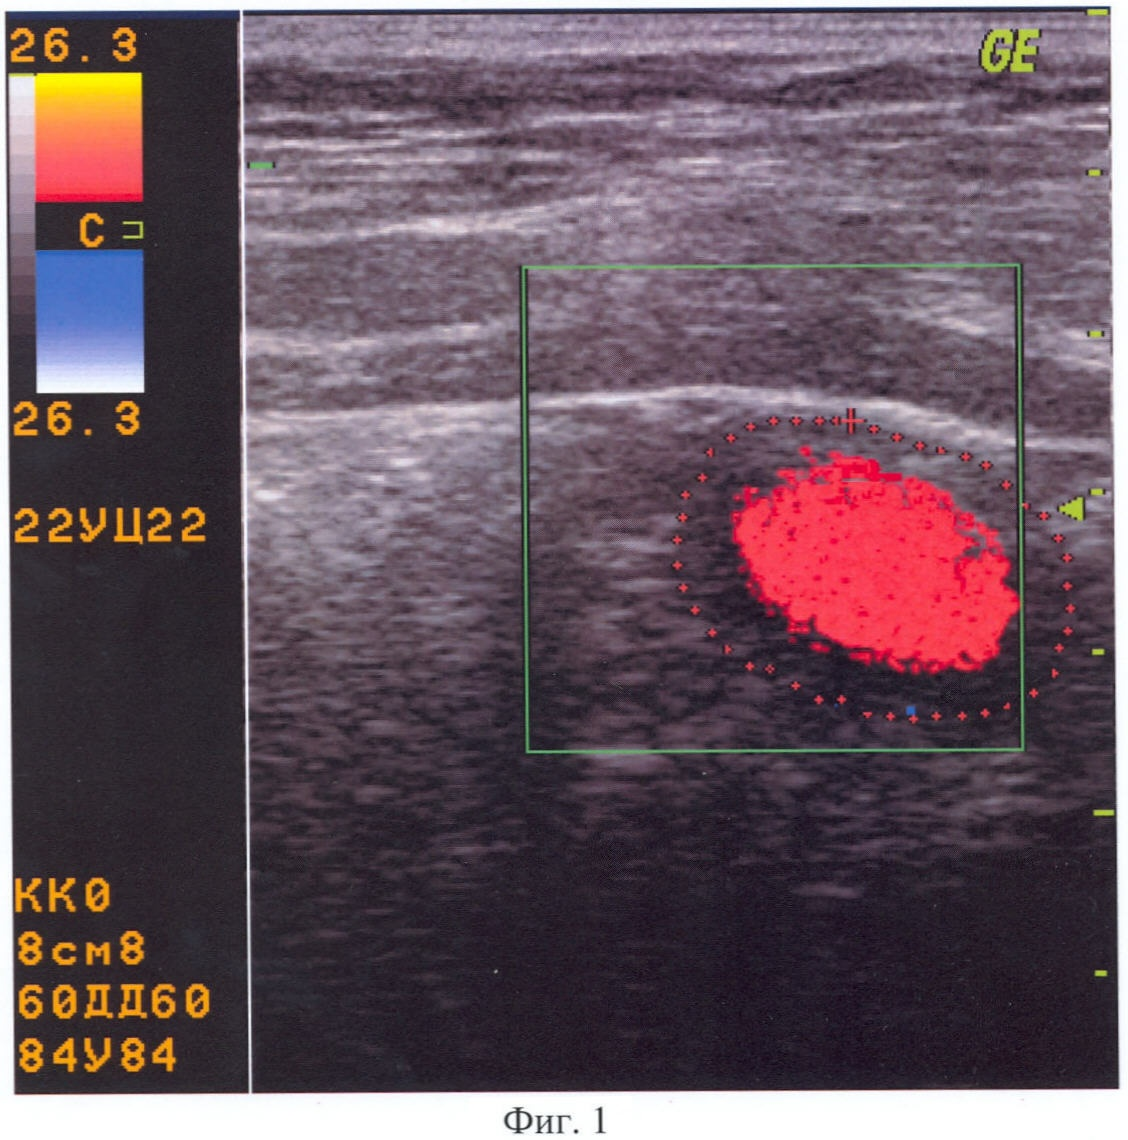

Далее в течение 180 секунд проводят непрерывную эхолокацию поперечного ультразвукового среза гастродуоденального перехода с цветовым доплеровским картированием внутрипросветного содержимого в режиме цветного дуплексного сканирования и регистрируют цвет внутрипросветного потока: при этом красный цвет показывает направление движения содержимого в антеградном направлении из желудка в двенадцатиперстную кишку, синий цвет показывает направление движения содержимого в ретроградном направлении из двенадцатиперстной кишки в желудок.

При регистрации красного прокрашивания внутрипросветного содержимого гастродуоденального перехода определяют отсутствие дуоденогастрального рефлюкса, как показано на Фиг.1.

При проведении ультразвукового исследования согласно предлагаемому способу, выявлены следующие параметры. Исходно: просвет гастродуоденального перехода сомкнут, содержимое не определяется. Осмотр после контрастирования: максимальный диаметр поперечного сечения гастродуоденального перехода составляет 21 мм, в его просвете определяется анэхогенное однородное содержимое (контрастное вещество). Привратник при прохождении перистальтической волны полностью смыкается. При непрерывной эхолокации в течение 180 сек в режиме цветового доплеровского картирования регистрируется красное прокрашивание внутрипросветного содержимого гастродуоденального перехода. Заключение: Дуоденогастральный рефлюкс отсутствует (Фиг.1).